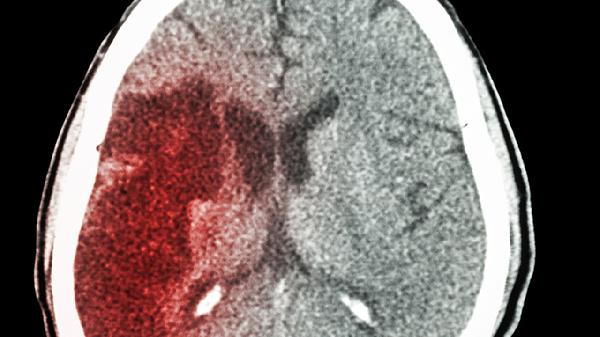

脑出血多因高血压或血管畸形导致血管破裂,起病急骤且症状迅速达高峰。常见剧烈头痛、呕吐、意识障碍,严重者可出现瞳孔不等大。CT检查可见高密度血肿,治疗需降低颅内压和控制出血,常用甘露醇注射液、氨甲环酸氯化钠注射液等药物,必要时需手术清除血肿。